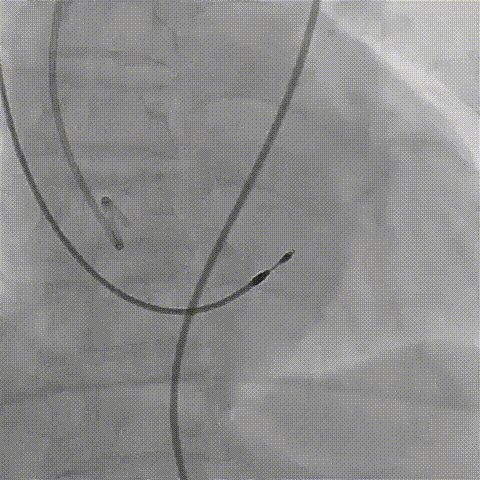

2026年伊始,TaurusTrio经导管主动脉瓣系统在复旦大学附属中山医院,浙江大学医学院附属第二医院,中国医学科学院阜外医院,首都医科大学附属北京安贞医院,四川大学华西医院等多家临床中心成功开展上市后全国首批植入。这不仅是TaurusTrio正式走向广泛临床应用的重要里程碑,更标志着中国单纯主动脉瓣反流介入治疗正式迈入了“心键合璧”的全新纪元。